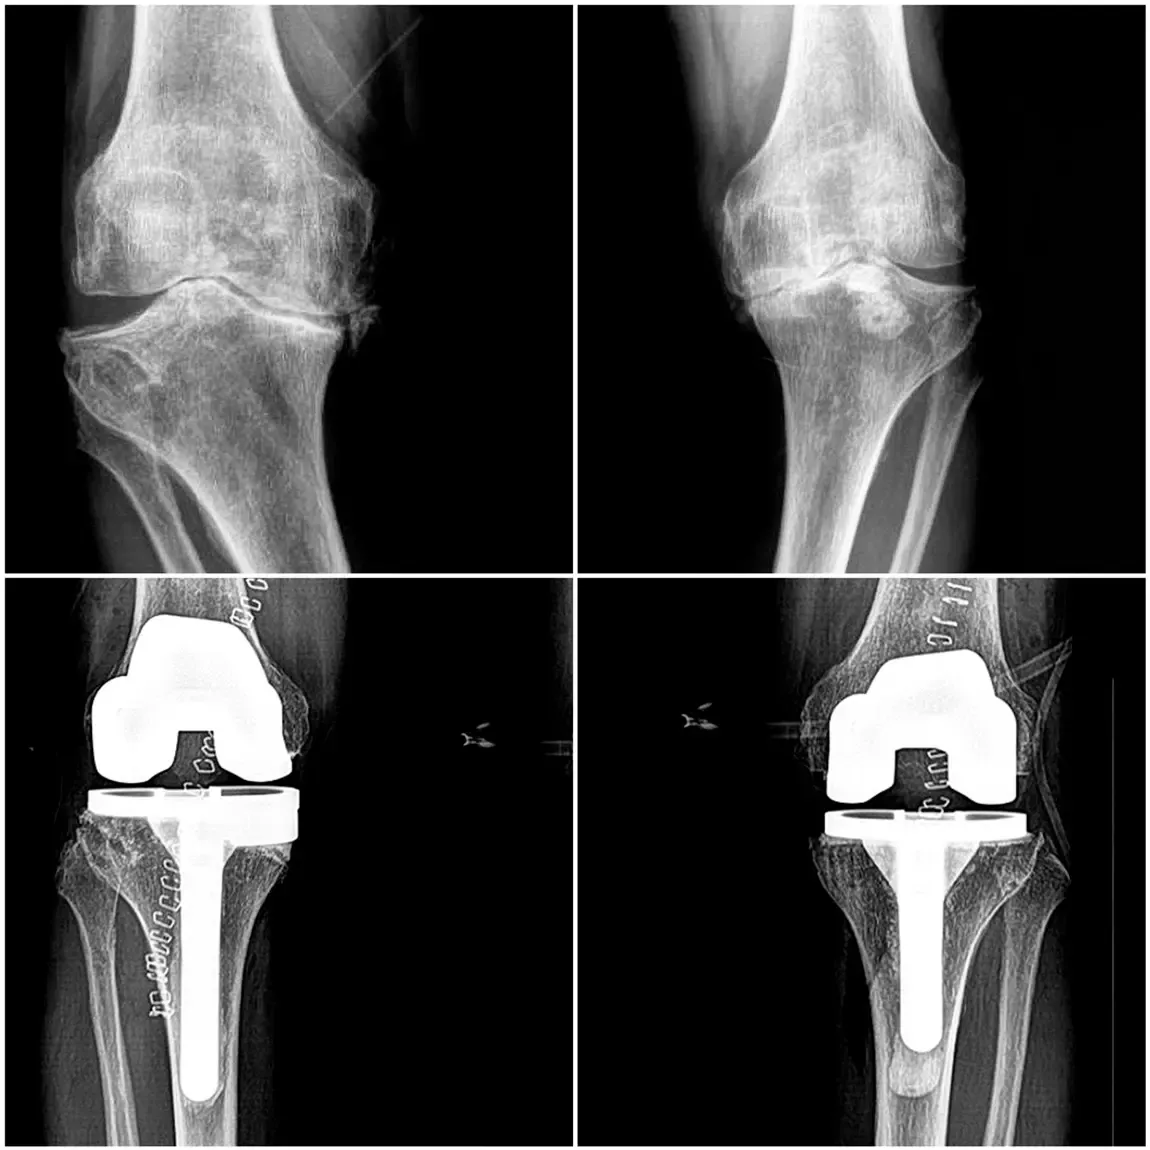

Reemplazo total de rodilla

Reemplazo total de rodilla (artroplastia total) prótesis total

Descripción: Sustitución de la articulación de la rodilla por una prótesis de componentes metálicos en fémur y tibia y un inserto tibial de polietileno de ultra alta densidad.

Indicado para:

• Artrosis severa, desgaste importante del cartílago, artritis reumatoide, artrosis post traumática.